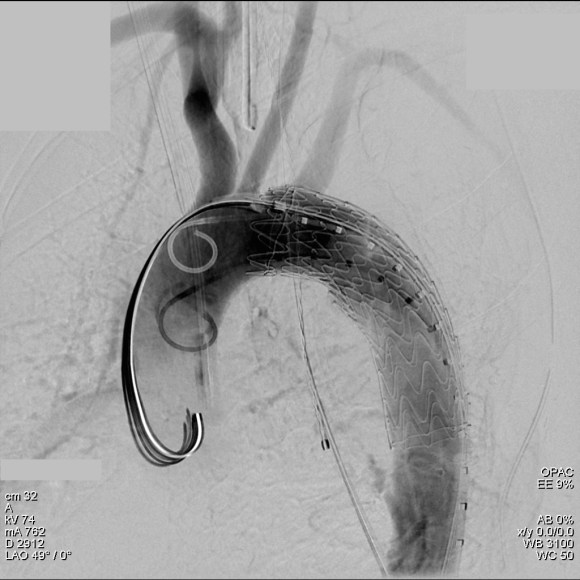

The patient was operated on in a hybrid endovascular OR suite. A right groin incision was made to expose the common femoral artery for endarterectomy and left common femoral access was achieved for angiographic access, but also to place a wire across the occlusion into the common femoral artery.

All actions on the external iliac artery plaque are done with an up-and-over wire, allowing for swift action in the instance that arterial perforation or rupture occur. This event is exceedingly rare when the operation is well planned. With this kind of access, an occlusive balloon or repairing stent graft can be rapidly delivered.

The common femoral endarterectomy is done from its distal most point and the Vollmer ring is used to mobilize the plaque. A Moll Ring Cutter (LeMaitre Vascular) is then used to cut the plaque.

The plaque is extracted and re-establishes patency of the EIA.

The plaque end point is typically treated with a stent -in this case, the common iliac plaque was also treated.